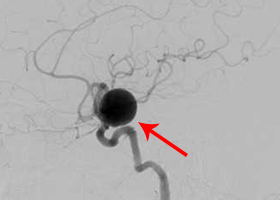

動脈瘤(赤矢印) -

手術中の脳血管撮影画像

(手術前) -

クリップ留置後、瘤(こぶ)は消失 -

(手術後) -